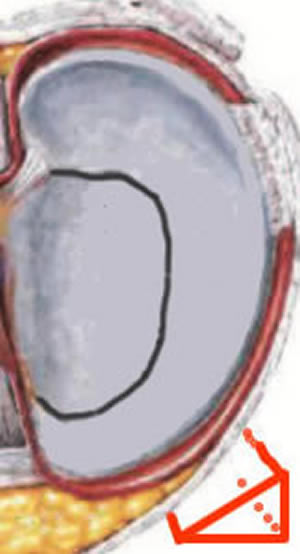

Le ménisque normal

Dessin d'un ménisque normal, vu du dessus